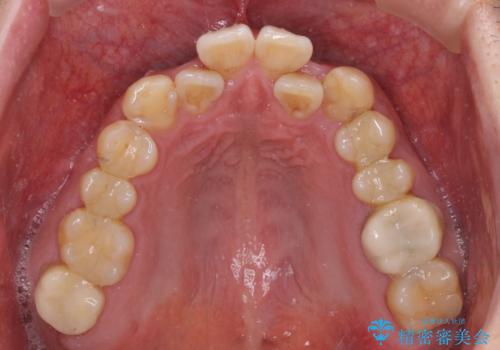

- 虫歯が多く、セラミッククラウンにより虫歯治療を行っている途中で矯正治療をしたいとのことで来院された患者様です。

虫歯治療途中の歯は仮歯が装着されていたため、そのまま矯正治療を行い、矯正後に補綴治療を行うこととしました。

インビザライン矯正では苦手とする舌側転位した前歯をスムーズに改善することができました。